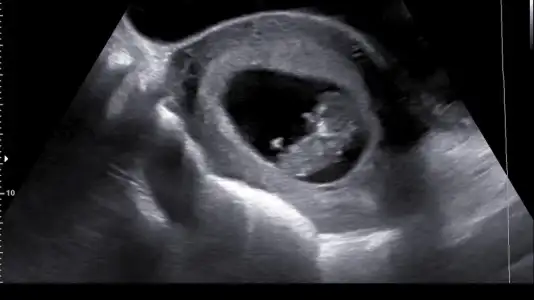

Benim bebeğime de bakar mısınız 12+4 günlük burada doktor cinsiyetini göremedii sizce nedir

Eklentiler